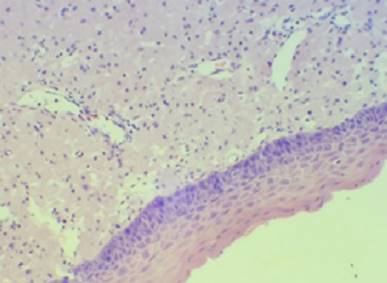

El estudio anatomopatológico muestra una proliferación difusa de células de gran talla con citoplasma amplio y granular, con núcleos pequeños, algunos lateralizados. Se encuentra revestida por una delgada capa mucosa pavimentosa que muestra focos de ulceración. Presenta rica red vascular estromal. Se solicita técnica de PAS (ácido peryódico de Shiff) que es positiva en el citoplasma de las células granulares (Figura 3). La inmunomarcación con la proteína S100 es negativa en las células de la proliferación (Figura 4). Estos hallazgos son consistentes con el diagnóstico de tumor de células granulares congénito (épulis congénito).

Figura 3: 100x, hematoxilina-eosina. Proliferación compuesta por células con citoplasma granular y estroma ricamente vascular, revestido por una delgada capa mucosa.